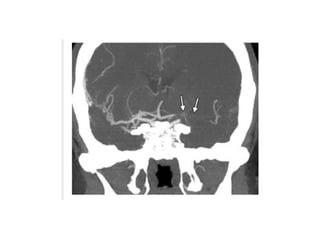

CTA

CT Angiography

• For assessment of intracranial and extracranial

circulation

• Can demonstrate thrombi

• Timed bolus of contrast for vessel enhancement

• Can guide decision regarding intraarterial or mechanical

thrombolysis by quantifying clot burden

Normal CT Angiography